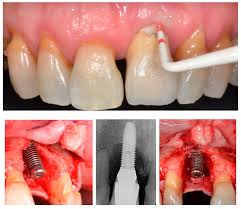

Peri-implant Disease

“….It is absolutely crystal clear the patients who attend for routine maintenance get very little amounts of Peri-implant disease and the disease that they get is hugely treatable.

Whereas it is also absolutely clear that if they don’t attend the incidents of Peri-implant disease goes through the roof.

….Peri-implant disease is a real reality even in the practices of people who do it properly, but for those who don’t it will be a disastrous long-term complication.”